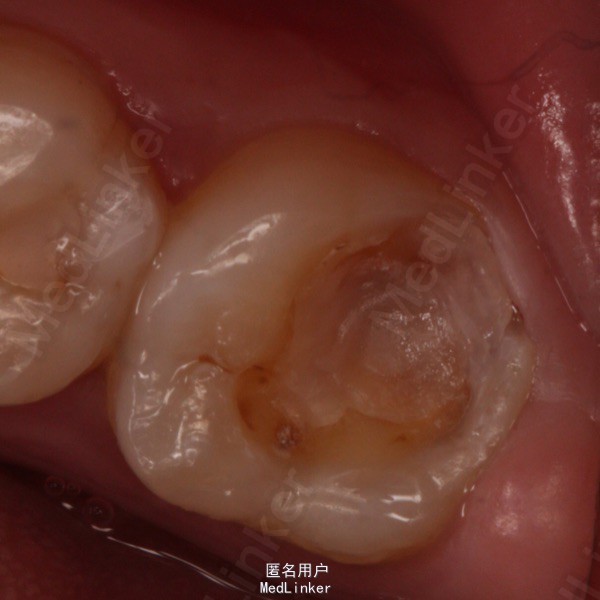

主诉:右下后牙补料脱落1周余。 现病史:多年来,右侧后牙因龋反复充填治疗,一周前补料复又脱落,否认疼痛史,就诊我科。

检查,47 牙合 面及远舌轴面深大龋洞,探诊敏感,未见穿髓孔,冷(—),叩痛(—),余未见异常

诊断:47深龋伴牙体缺损 处理:47激光去腐,脱敏,硅橡胶取模,预瓷嵌体修复。